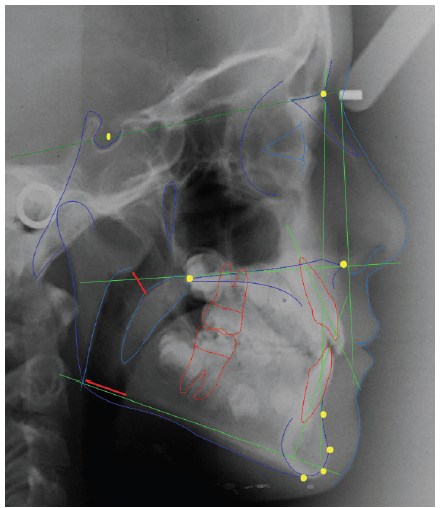

The following cephalometric measurements were evaluated: SNA, SNB, ANB, SN.GoGn, SN.PP, 1.PP and 1.PM (McNamara Jr., 1984) (Figure 2). The lateral cephalograms were scanned (HP Scanjet G4050, USA) and imported to a cephalometric analysis program (Cef X, CDT Softwares, Campo Grande, Brazil) (Figure 1). Intercanine and intermolar distances were measured on the plaster casts at T0, T1, T2 and T3 with the aid of a digital caliper (precision: 0.01 mm) (Mitutoyo-Japan). Four measures were made: A) gingival intermolar distance (union between palatal gingival margin and tooth); B) cusp intermolar distance (mesiopalatal cusps); C) gingival intercanine distance; and D) cusp intercanine distance (Lagravere, Major, Flores-Mir, & Orth, 2005) (Figure 3). The difference between the cusp and gingival measures allowed the determination of whether RME caused inclination of the teeth. One month after first measures, 50% of the lateral cephalograms and dental casts were randomly selected and the measures were repeated.

None of the cephalometric measures underwent any significant change among the four periods evaluated (T0, T1, T2 and T3) (Table 1). Moreover, no significant differences in these measures were found in comparison with the CG (Table 2).